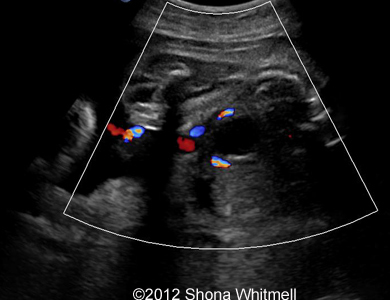

Figure 5: 2-umbilical arteries along the bladder.

Image-15